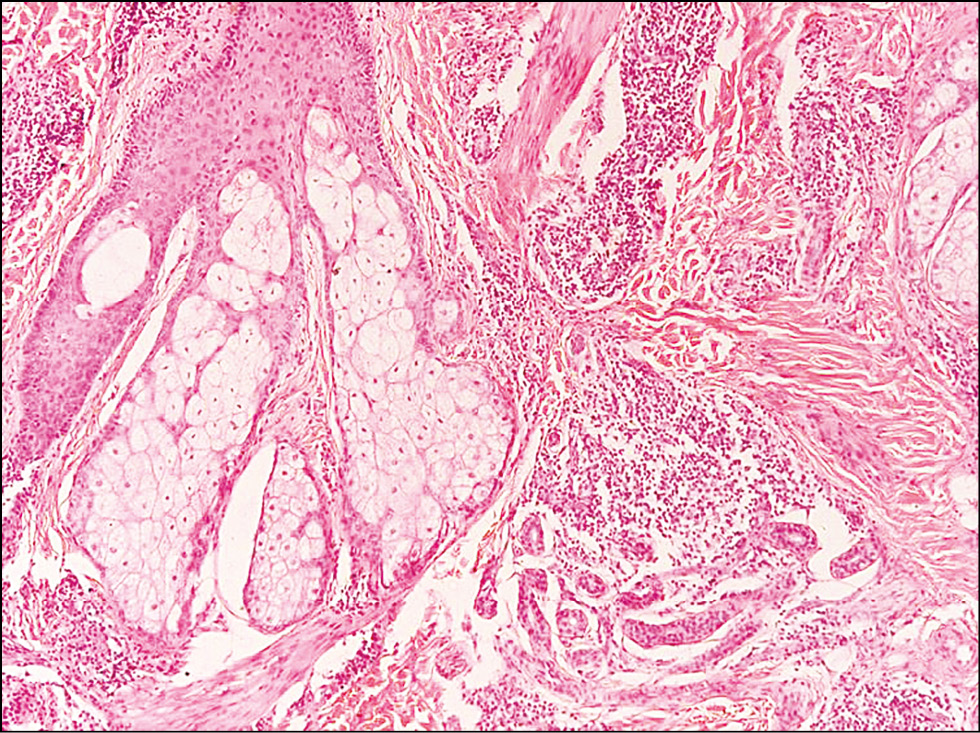

Изучение патоморфологических особенностей ДЛК позволило выделить её основные черты. Лимфоцитарный инфильтрат, состоящий преимущественно из малых В-лимфоцитов, плазматических клеток, гистиоцитов, макрофагов, нейтрофильных и эозинофильных форм гранулоцитов, в большинстве случаев располагался в верхних (n=16; 53%) и средних (n=11; 36,7%) слоях дермы, однако при ДЛК, представленной узлами (n=3; 10%), он распространялся и на подкожно-жировую клетчатку (рис. 6). Во всех случаях наблюдалась сохранность придатков кожи с перифокальными инфильтратами, а также пролиферация микрососудов (рис. 7). Из 30 больных ДЛК у 8 (26,7%) в коже были обнаружены фолликулоподобные структуры (рис. 8), у 6 (20%) ― лимфоидные фолликулы с герминативными центрами (рис. 9). Лимфоидные фолликулы различных размеров имели характерные чёткие границы с широким ободком из мелких лимфоцитов. В герминативном центре лимфоидных фолликулов наблюдались многочисленные митозы. При иммуногистохимическом исследовании кожи в биоптатах всех больных ДЛК в дермальном инфильтрате было выявлено преобладание CD20+ В-лимфоцитов (рис. 10) Соотношение IgL κ/λ составило примерно 1:1 во всех биоптатах (рис. 11, 12). По результатам ПЦР-анализа: по реаранжировкам генов IgH B-клеточная клональность не выявлялась в большинстве случаев (n=25; 83%), в 5 (17%) ― результат был интерпретирован как сомнительный.

Рис. 7. Патоморфологические особенности доброкачественной лимфоплазии кожи с неустановленной причиной: лимфогистиоцитарный инфильтрат располагается вокруг сально-волосяного фоллликула, ×100. / Fig. 7. Pathomorphological features of benign lymphoplasia of the skin with an unknown cause: сutaneous lymphoid hyperplasia, unknown cause. Lymphohistiocytic infiltrate around the sebaceous hair follicle, ×100.